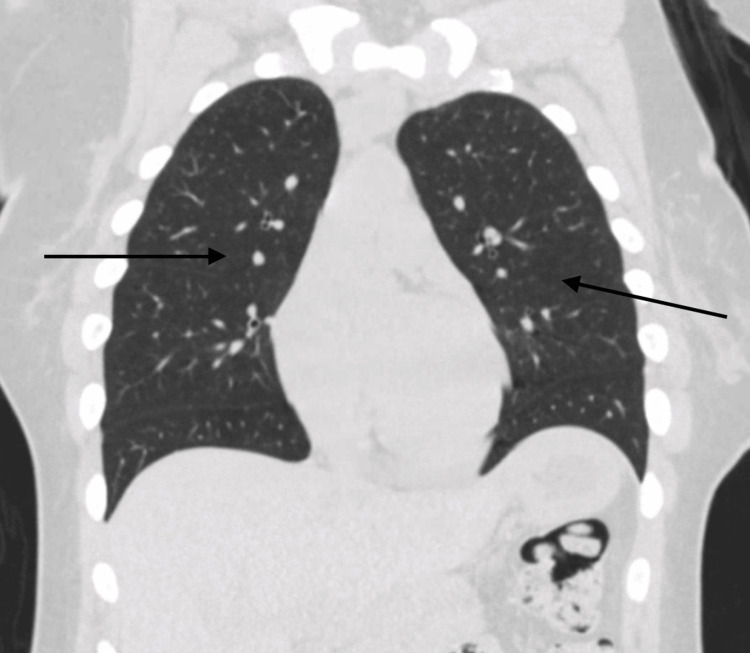

On initial evaluation, the patient was alert and oriented but noted to be hypoxic with oxygen saturation of 91% on room air and required supplemental oxygen. Chest X-ray initially revealed bilateral patchy opacities (Figure 1), and contrast-enhanced computed tomography (CT) of the chest revealed diffuse ground-glass opacities (GGOs) (Figure 2). Laboratory tests showed an initial hemoglobin level of 13.3 g/dL, which precipitously dropped to 9.3 g/dL (reference range: 12.0-16.0 g/dL) within 24 hours. Urine toxicology was positive for cannabis, while renal function and coagulation studies were unremarkable.

Typical pulmonary radiological findings of DAH include diffuse bilateral alveolar infiltrates, which are often described as GGOs on chest CT scans or consolidations on chest X-rays. However, in the early stages, chest X-rays can fail to capture the full extent of the disease, and serial X-rays or chest CT should be considered for a prompt and accurate diagnosis. The infiltrates observed in DAH are typically patchy or confluent and can progress rapidly, reflecting the alveolar spaces filling with blood. This pattern is usually non-segmental and predominantly affects the dependent lung regions [ref. 10].

Chest CT is more sensitive than chest X-rays in detecting the features of DAH. GGOs, as seen on CT scans, are more prominent and provide a clearer delineation of the extent of alveolar hemorrhage compared to consolidations. Unlike infectious pneumonia, the infiltrates in DAH generally lack air bronchograms, which can aid in distinguishing between these conditions. In the acute setting, chest imaging may appear normal in up to 50% of cases, which highlights that normal radiological findings do not rule out the diagnosis. Rapid imaging assessment combined with clinical evaluation is crucial for timely identification and intervention in cases of DAH [ref. 11].